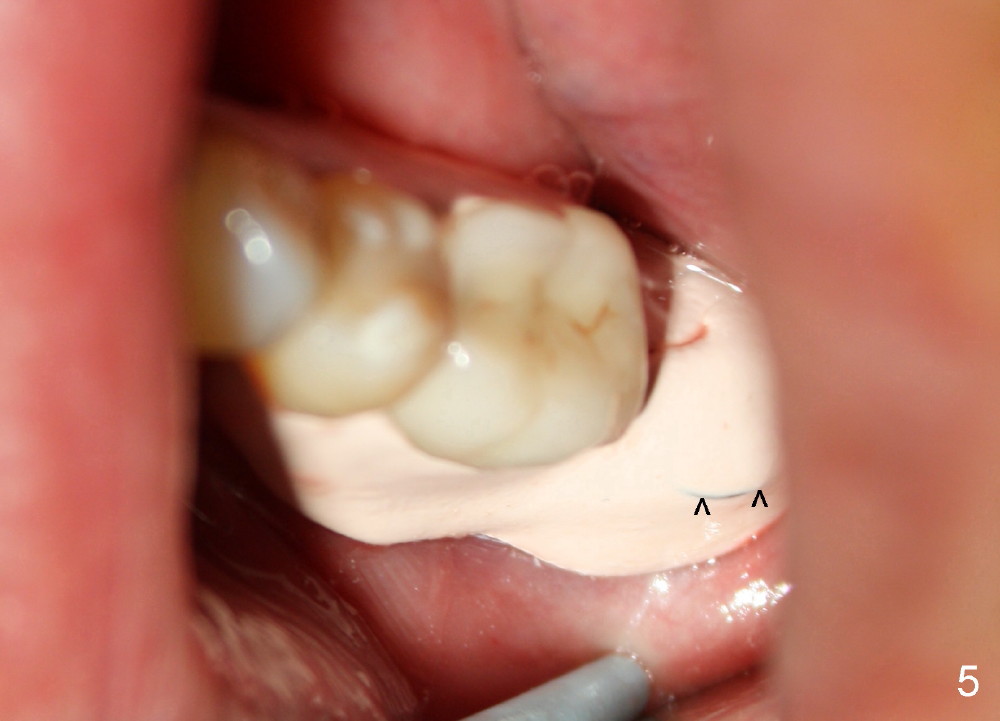

Approximately 1 mm coronal portion of the implant is exposed buccally and lingually. The exposed portion is covered by autogenous graft harvested during osteotomy and collagen membrane. The membrane is fixated between the implant and healing abutment (8.2(4(3)) (Fig.4). There are two unexpected advantages associated with using the healing abutment. The first is that the abutment reduces tension in suturing. The second is that perio dressing can be tucked underneath the hemisphere of the the large (8.2 mm) and tall (4 mm) abutment (Fig.5 ^). The dressing is more secure. It should not be dislodged in a week postop.